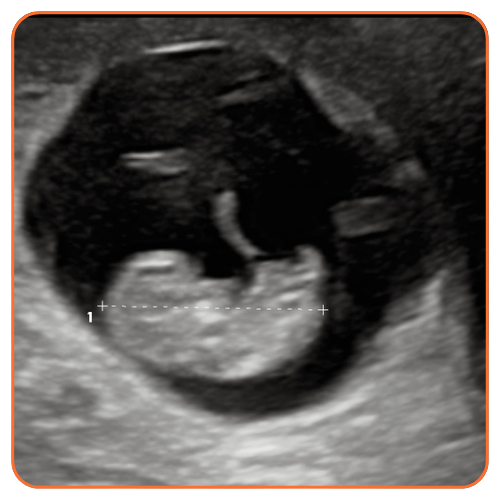

A view into the womb via an ultrasound and her baby’s heartbeat was what the Lord used to demonstrate the humanity of Emily’s baby, Avila said in a message to supporters, and now Emily will celebrate her first Mother's Day.

“Then, after they brought me and my boyfriend to the room and I saw my baby on that ultrasound,” she recalled, “and it was very emotional, because it’s my baby. Me and my boyfriend made that baby.”